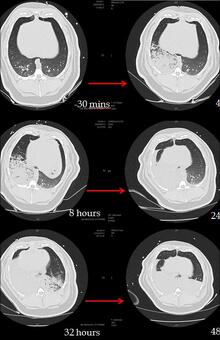

CT analysis of an OP and GJ pig lungs show the direct and indirect effects of aspiration over time (figure 2).

Figure 2: Time series CT lung scans taken from one pig at -30 minutes (before aspiration) to 48 hours after instillation of 0.5mls/kg mixture of OP and gastric juice in the right lung at time 0 hours. Over time, the right lung becomes more consolidated and at 32 hours the left lung also starts to show an indirect injury. At 48 hours bilateral posterior consolidation and fluid in the fissures are apparent.